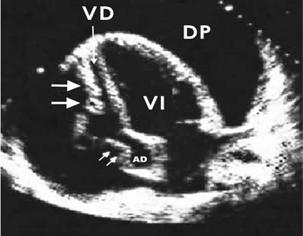

Ecocardiograma:

Aumento inexplicable de un espesor de la pared del ventrículo izquierdo ≥ 15 mm.

En las formas obstructivas, se observa el movimiento anterior sistólico (SAM) de la válvula mitral.